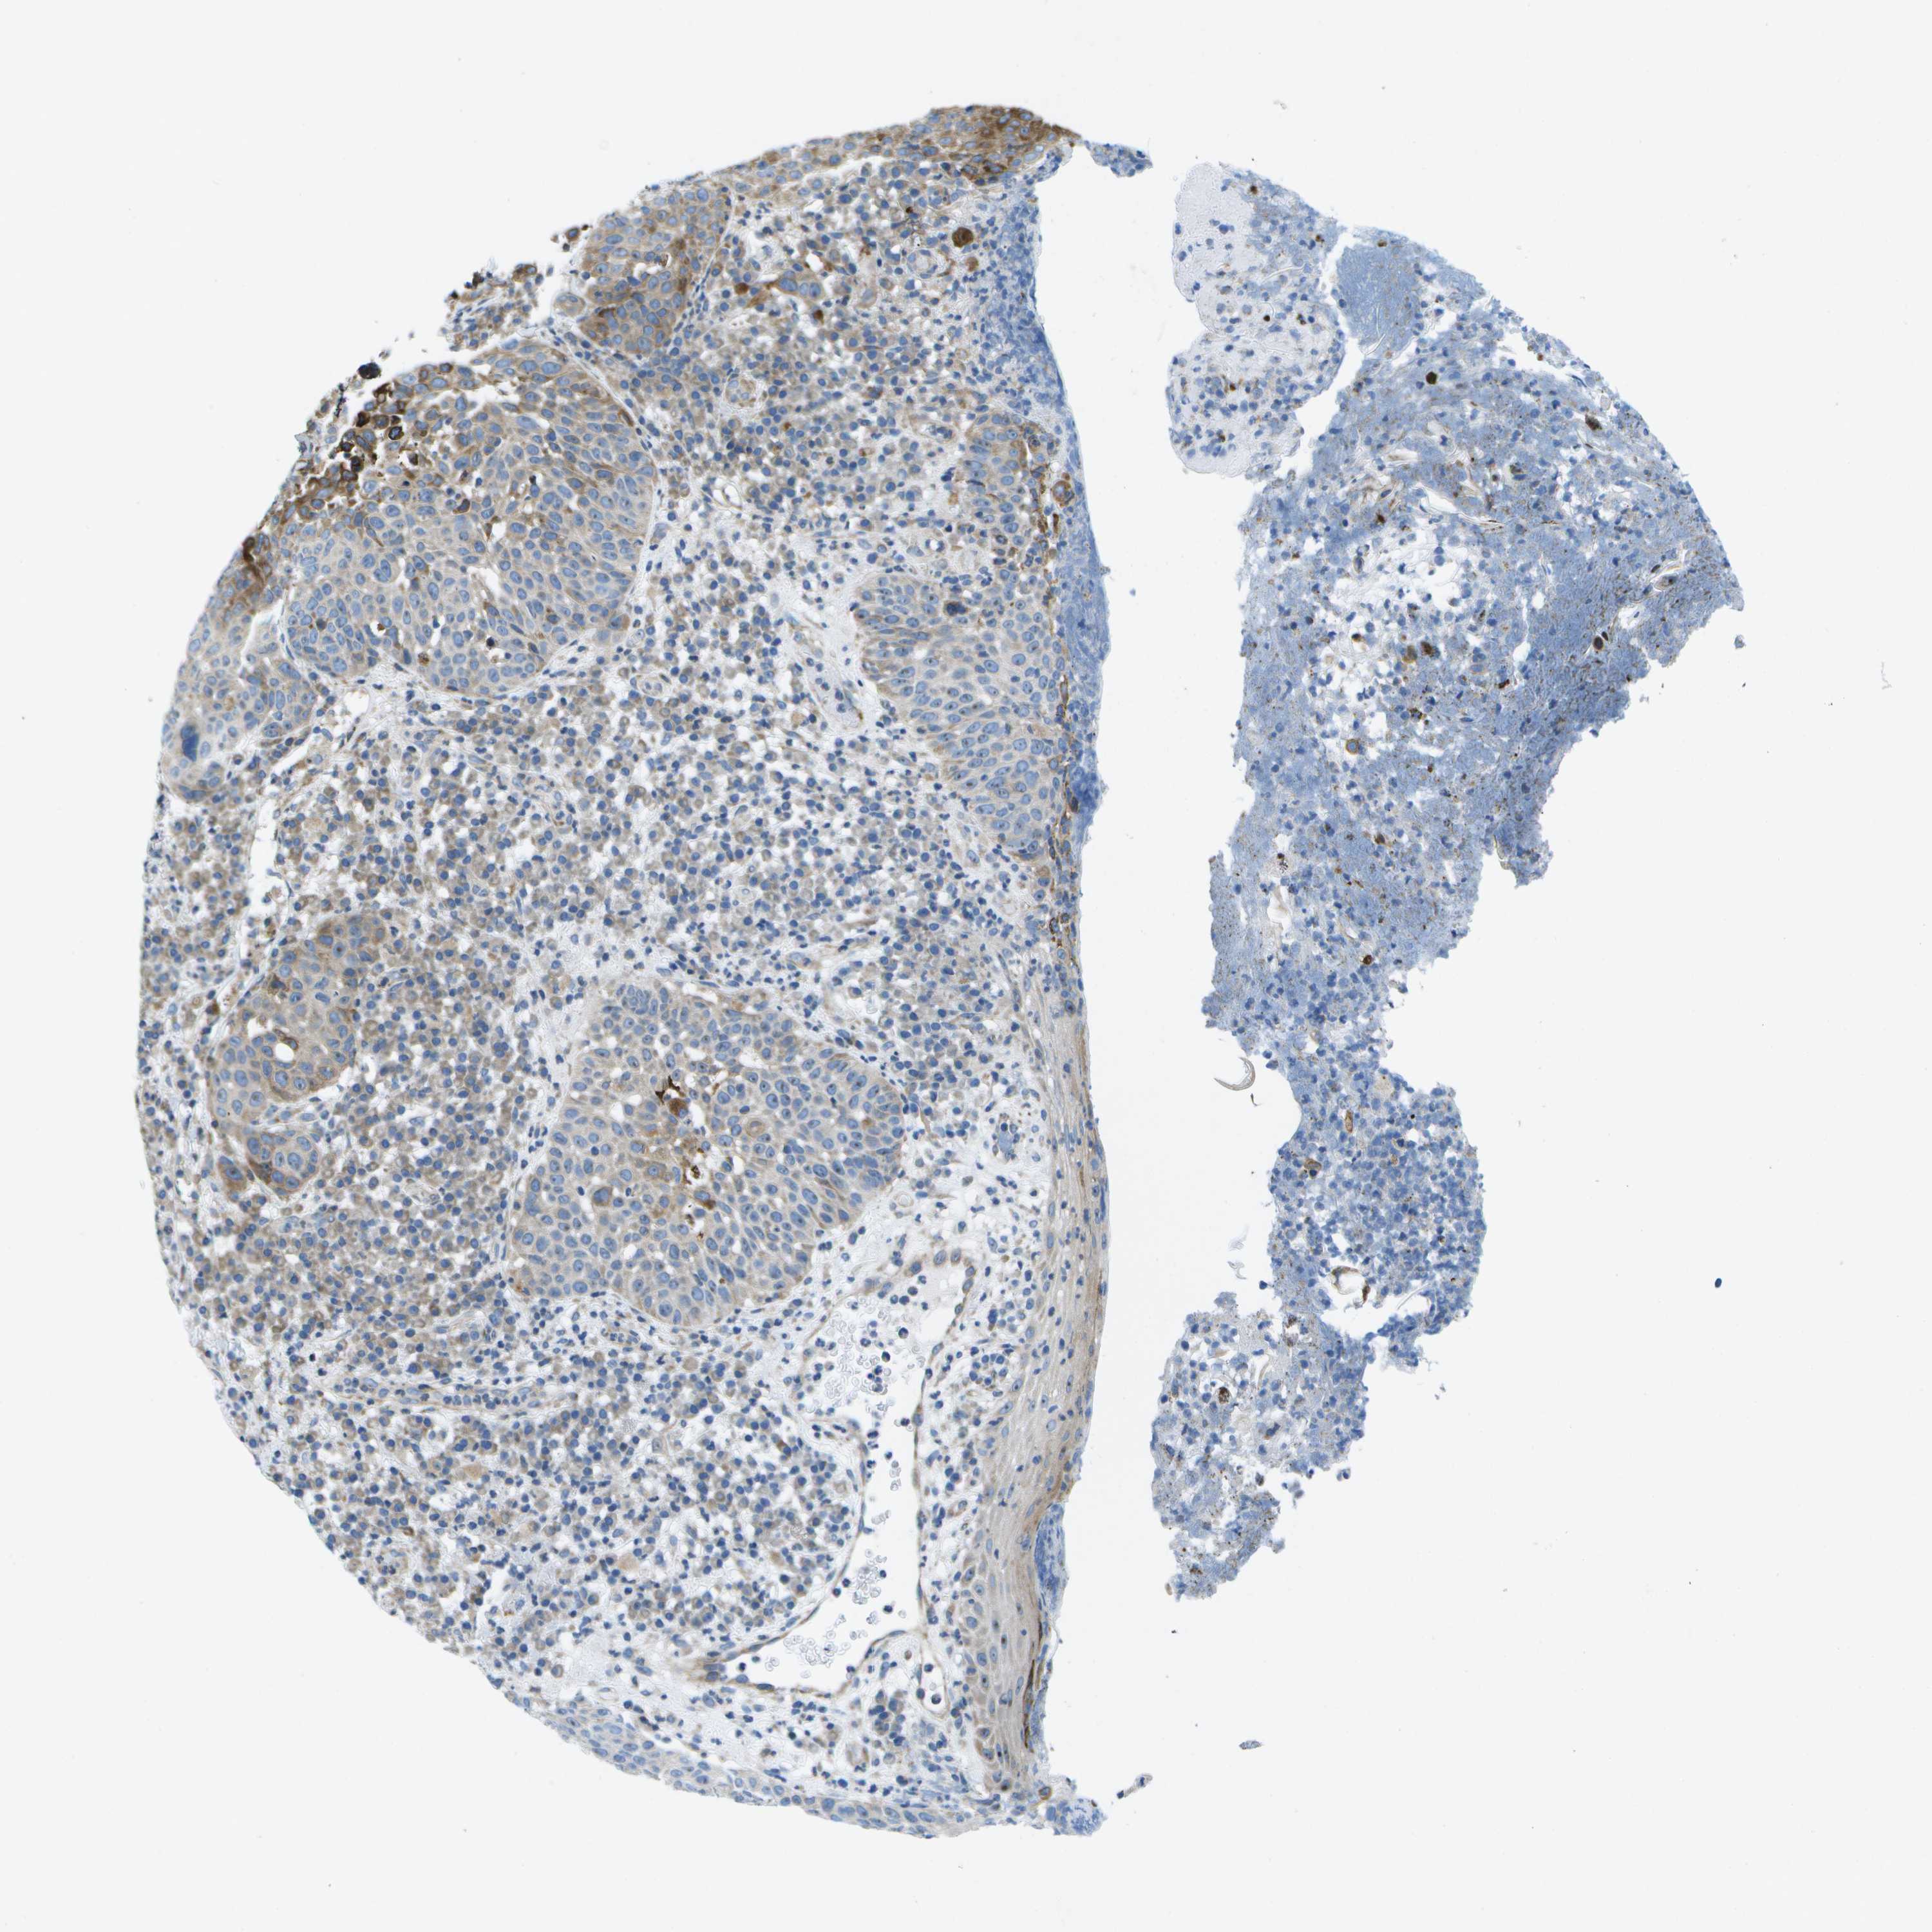

SKIN CANCER - Protein expressioni

A mouse-over function shows sample information and annotation data. Click on an image to view it in a full screen mode. Samples can be filtered based on level of antibody staining by selecting one or several of the following categories: high, medium, low and not detected. The assay and annotation is described here.

Antibody stainingi

Antibody staining in the annotated cell types in the current human tissue is reported as not detected, low, medium, or high, based on conventional immunohistochemistry profiling in selected tissues. This score is based on the combination of the staining intensity and fraction of stained cells.

Each image is clickable and will lead to virtual microscopy that enables deeper exploration of all samples and also displays staining intensity scores, fraction scores and subcellular localization as well as patient and tissue information for each sample.

Antibody HPA015648

Staining

High

Medium

Low

Not detected

Intensity

Strong

Moderate

Weak

Negative

Quantity

>75%

75%-25%

<25%

None

Location

Nuclear

Cytoplasmic/membranous

Cytoplasmic/membranous,nuclear

Squamous cell carcinoma in situ, NOS

Squamous cell carcinoma, NOS

Squamous cell carcinoma, metastatic, NOS

Basal cell carcinoma

Adnexal tumor, benign